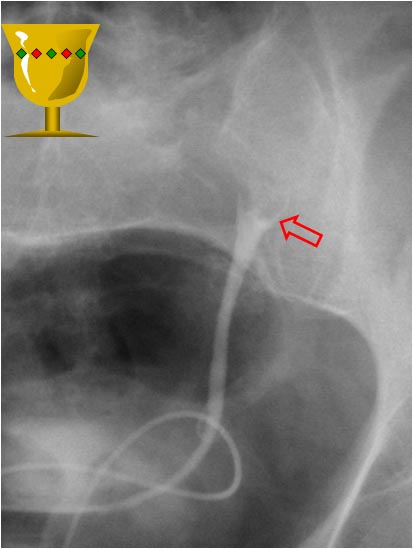

SIGNOS DE LA COLMENA Y DEL HERALDO

Signos de fístula colovesical en la cistografía. El extremo vesical de la fístula se asocia con la imagen de una deformidad biconvexa triangular (flechas verdes) que acaba en un punto bien definido, como si se insinuase el contraste en la boca de la fístula. De hecho puede verse contraste fuera de la vesícula, por encima de ese ángulo que forma el borde superior vesical.

En nombre del Signo de la colmena se debe a que la vejiga queda deformada adoptando una forma que recuerda a la celda de una colmena.

El Signo del heraldo es un signo temprano visible en el borde superior de la vejiga, en forma de semiluna. Es un hallazgo descrito en 1961 del que no hemos encontrado imágenes. Hemos marcado con flecha roja el borde semilunar de la vejiga, pero no sabemos si se trata en realidad de este hallazgo.

Heraldo en realidad significa “oficial o caballero que actuaba como mensajero o encargado de anunciar las noticias importantes” o “cosa que anuncia la llegada de otra”. Por ello algunos diarios han tomado este nombre, como El Heraldo de Aragón o el Herald Tribune. No vemos la relación entre este término y la deformidad de la vejiga descrita, a no ser que, al ser un signo precoz, anuncie la fístula antes de que sea visible.

También es posible que se trate de una mala traducción o una confusión entre heraldo y escudo heráldico. Por la forma de la imagen, que recuerda a un escudo o blasón, pensamos que el signo debiera llamarse, más bien, Signo del escudo heráldico.